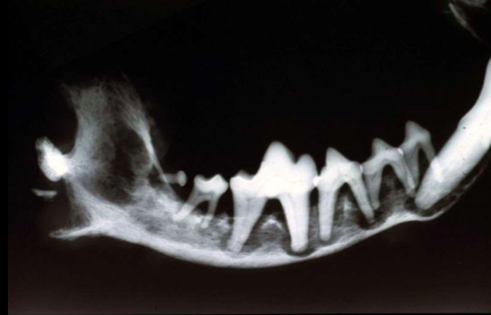

Name the condition and the cause!

Fibrous Osteodystrophy “Rubber Jaw”

Caused by Renal Failure

Describe whats going on in the bone!

Osteolysis

Name the Disease!

Rubber Jaw! (Fibrous Osteodystrophy)